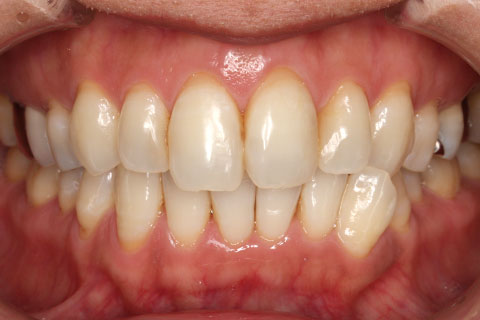

オールセラミックの症例2

- 年齢・性別

- 45歳男性

- 治療期間

- 2ヶ月

- 抜歯

- なし

- 治療費

- 70.4万円

- 備考

- 前歯8本の歯列不正によるセラミック治療

- 治療内容

- 歯質を削除し、セラミック冠をセメント合着

- 施術の副作用(リスク)

- 知覚過敏、歯髄炎、荷重負担